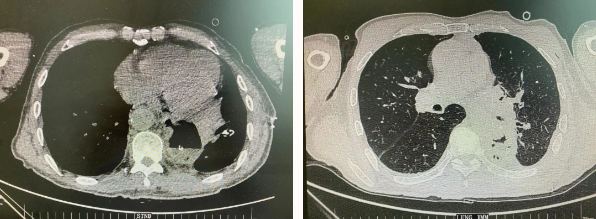

患者王某不幸同時患食管癌與左肺癌,病理類型系雙源發(fā)腫瘤,食管為鱗癌、肺為腺癌。食管癌和肺癌為胸外科最常見的疾病,但同時患兩種疾病,十分罕見。家屬輾轉多個醫(yī)院,得知李小飛院長擅長胸外科復雜手術,慕名來西安國際醫(yī)學中心醫(yī)院。

經(jīng)過李小飛教授、李文海副教授、穆強副主任醫(yī)師團隊積極準備,排除手術禁忌;經(jīng)過全科術前充分討論,大家認為:如果分兩次進行手術,另一種疾病勢必會受到影響,腫瘤可能進展。胸外科手術對呼吸循環(huán)影響較大,同期實施兩個手術更要小心謹慎。李小飛教授主持術前討論,設計合理手術方式,由于食管癌胸腔鏡手術為右側入路,但為兼顧左肺癌手術,則采用傳統(tǒng)左開胸手術。

2022年4月25日,由李小飛教授主刀,同期行左側開胸:食管癌根治術 左肺癌根治術,一次手術同時根治兩種惡性腫瘤疾病。經(jīng)過精細手術及術后管理,患者術后十天,恢復良好,進食良好,現(xiàn)已出院。